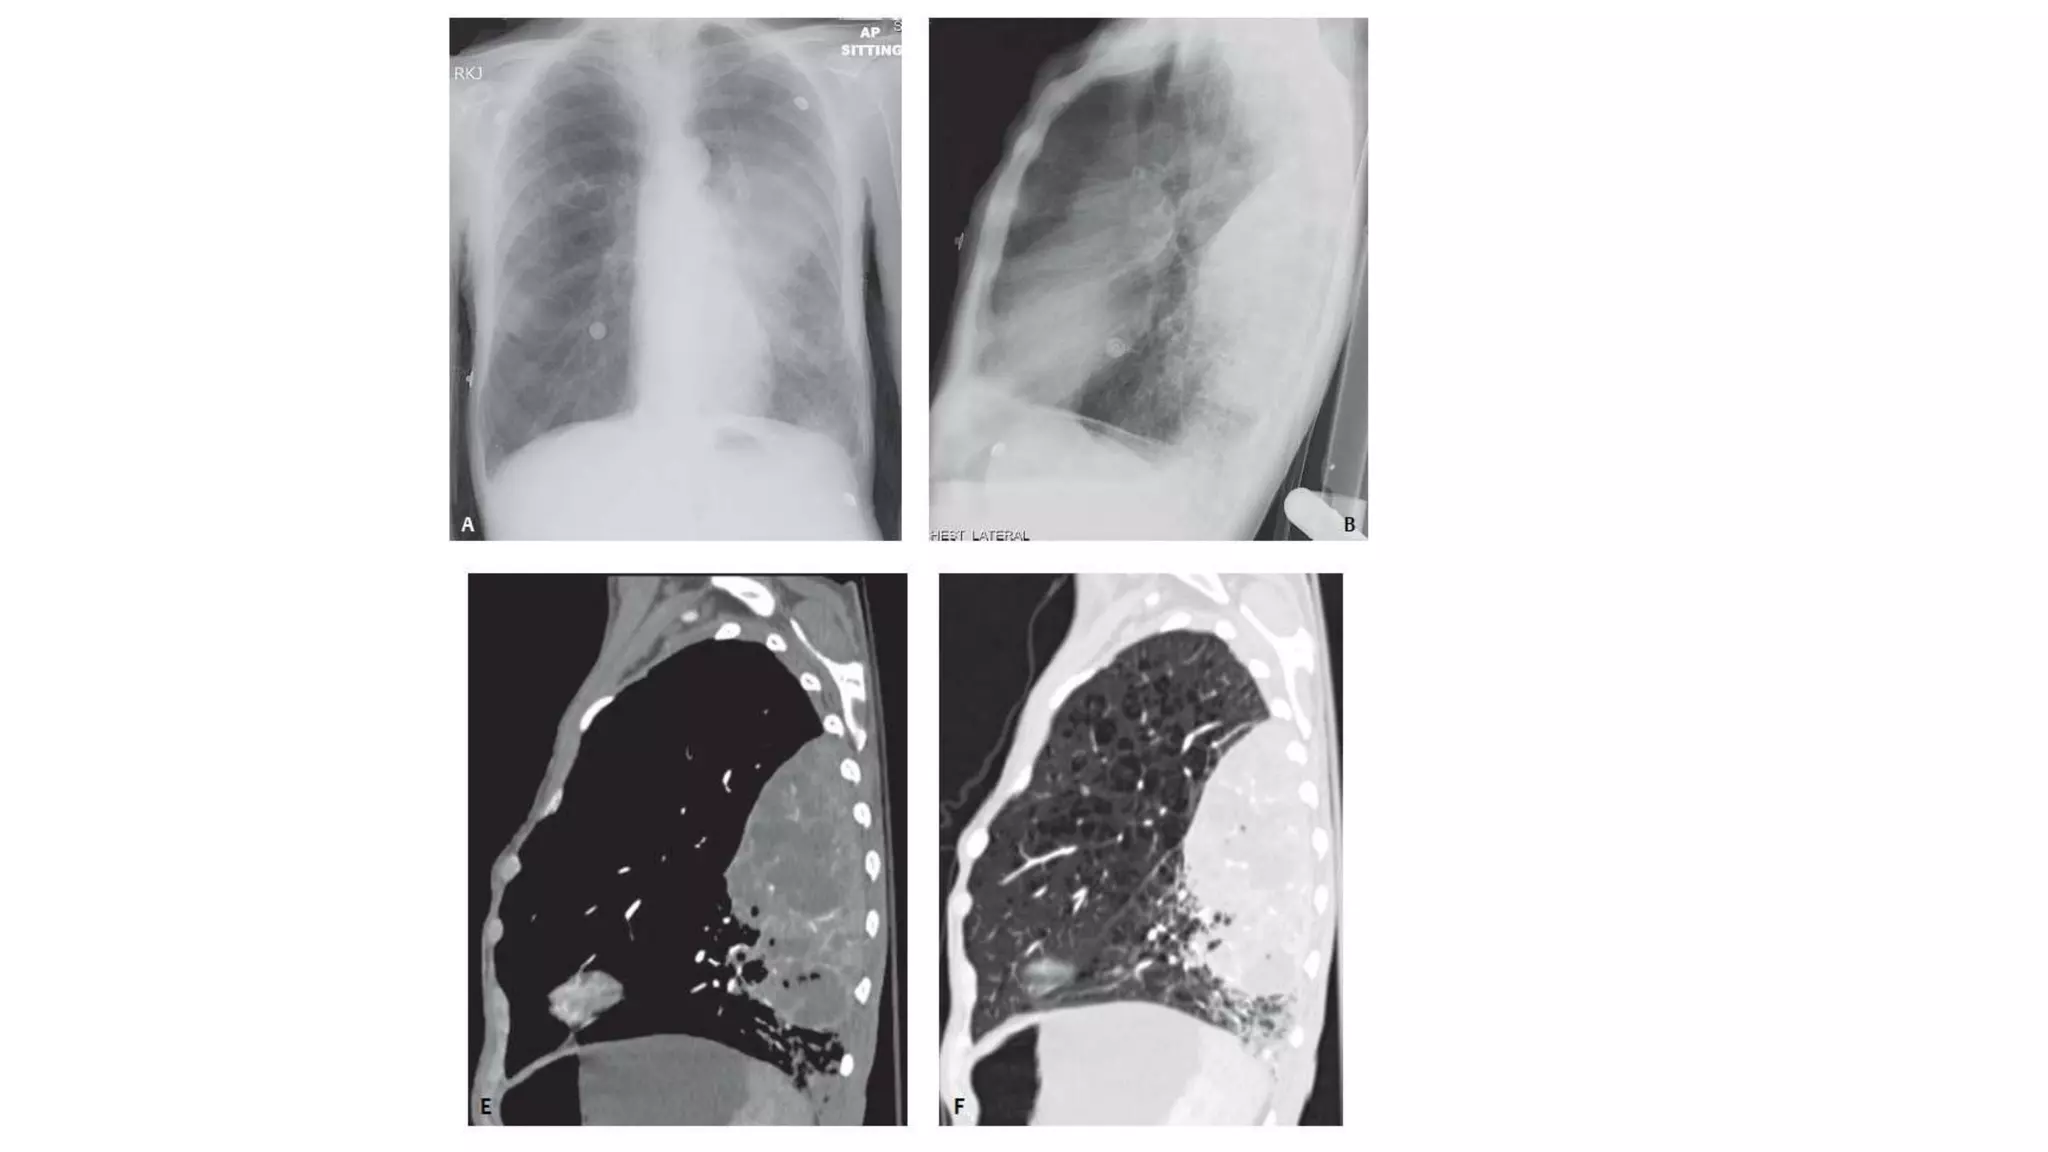

PA chest radiograph of a 9-year-old boy with tuberculosis

demonstrates a coalescent right perihilar consolidation

with ipsilateral hilar and mediastinal lymphadenopathy

PA chest radiographof a 9-year-old boy with tuberculosis demonstrates a coalescent right perihilar consolidation with ipsilateral hilar and mediastinal lymphadenopathy